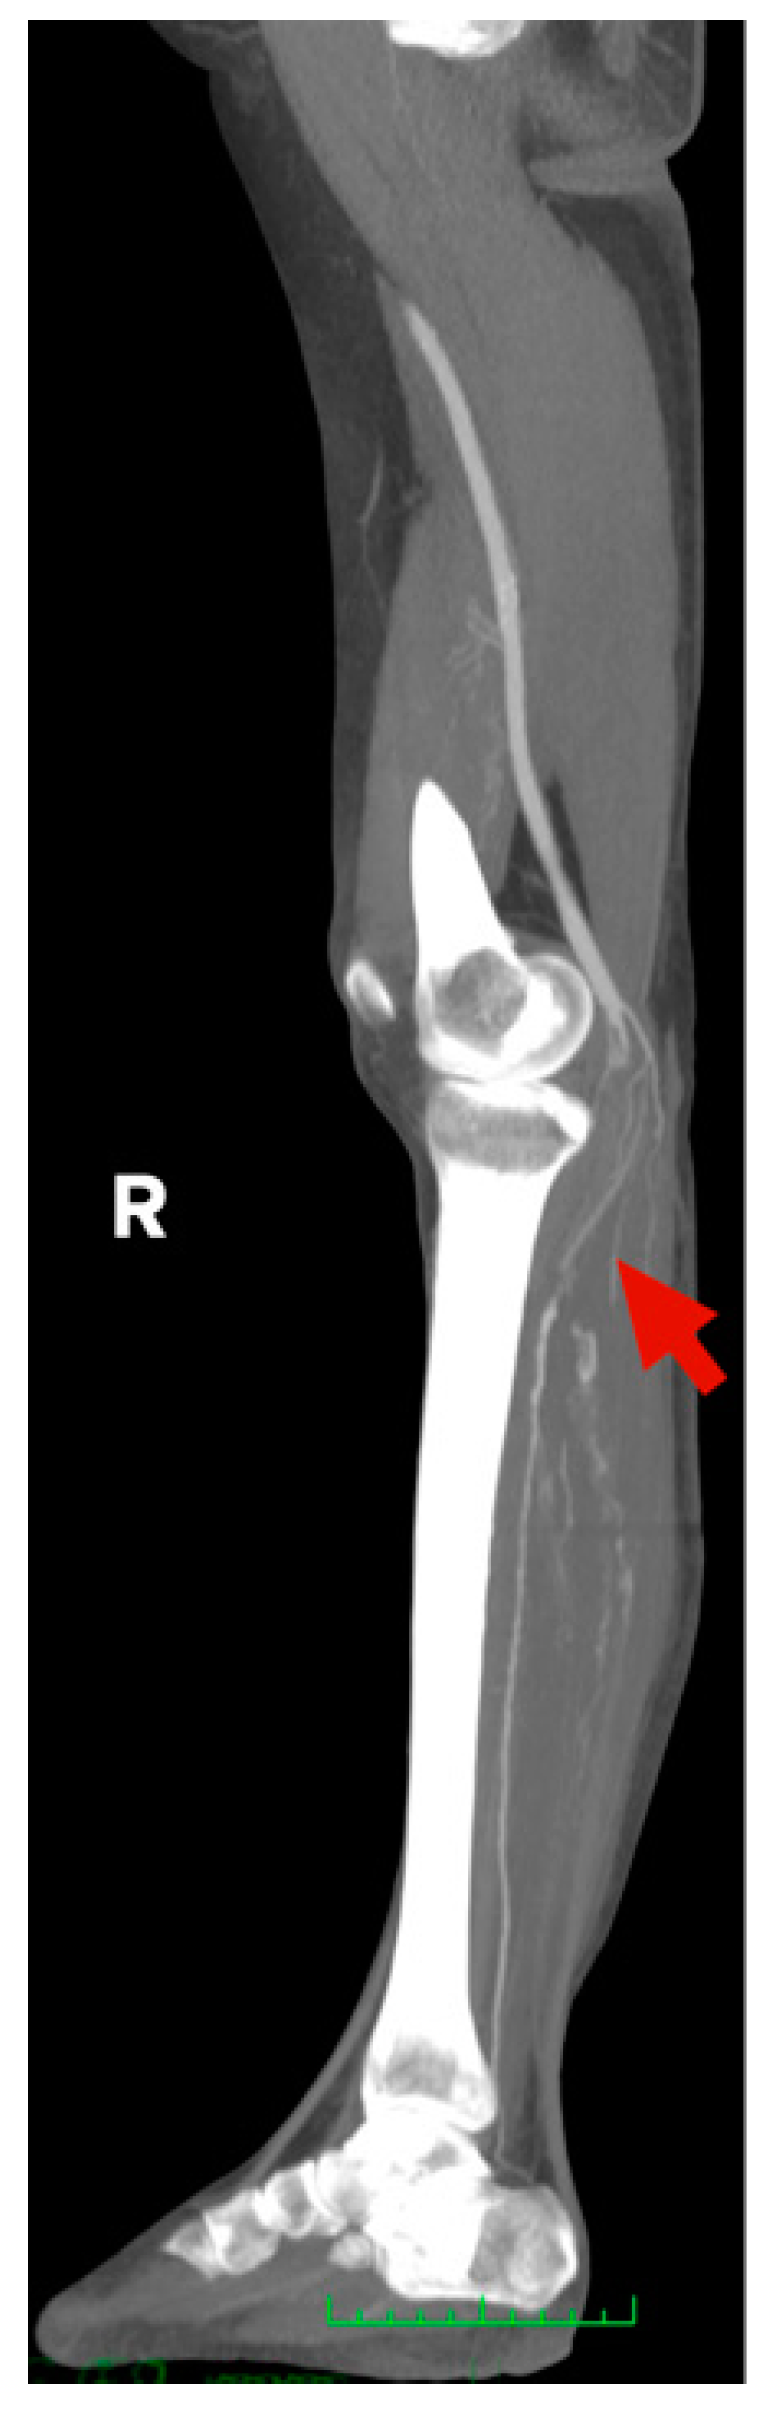

Figure 3.

CT-Angio of 58 yo female with stage IIB acute right lower limb ischemia 14 days after SARS-CoV-2 infection.